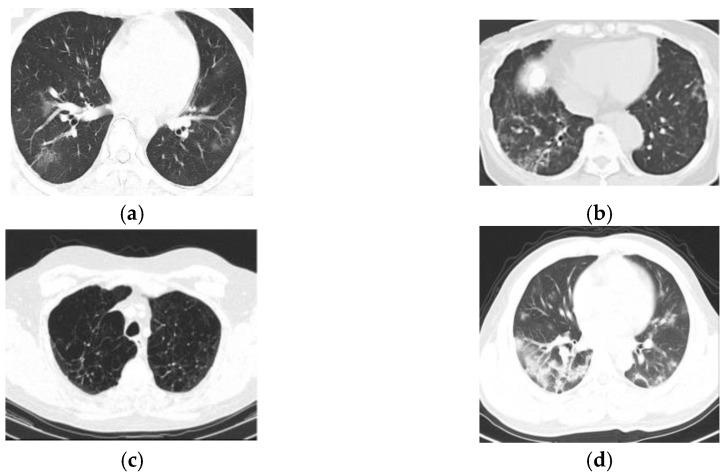

利用 CT 图像对 COVID-19 肺部感染严重程度进行识别和分类的 Remora Namib 甲虫优化深度学习

Remora Namib Beetle Optimization Enabled Deep Learning for Severity of COVID-19 Lung Infection Identification and Classification Using CT Images.

Coronavirus disease 2019 (COVID-19) has seen a crucial outburst for both females and males worldwide. Automatic lung infection detection from medical imaging modalities provides high potential for increasing the treatment for patients to tackle COVID-19 disease. COVID-19 detection from lung CT images is a rapid way of diagnosing patients. However, identifying the occurrence of infectious tissues and segmenting this from CT images implies several challenges. Therefore, efficient techniques termed as Remora Namib Beetle Optimization_ Deep Quantum Neural Network (RNBO_DQNN) and RNBO_Deep Neuro Fuzzy Network (RNBO_DNFN) are introduced for the identification as well as classification of COVID-19 lung infection. Here, the pre-processing of lung CT images is performed utilizing an adaptive Wiener filter, whereas lung lobe segmentation is performed employing the Pyramid Scene Parsing Network (PSP-Net). Afterwards, feature extraction is carried out wherein features are extracted for the classification phase. In the first level of classification, DQNN is utilized, tuned by RNBO. Furthermore, RNBO is designed by merging the Remora Optimization Algorithm (ROA) and Namib Beetle Optimization (NBO). If a classified output is COVID-19, then the second-level classification is executed using DNFN for further classification. Additionally, DNFN is also trained by employing the newly proposed RNBO. Furthermore, the devised RNBO_DNFN achieved maximum testing accuracy, with TNR and TPR obtaining values of 89.4%, 89.5% and 87.5%.

摘要